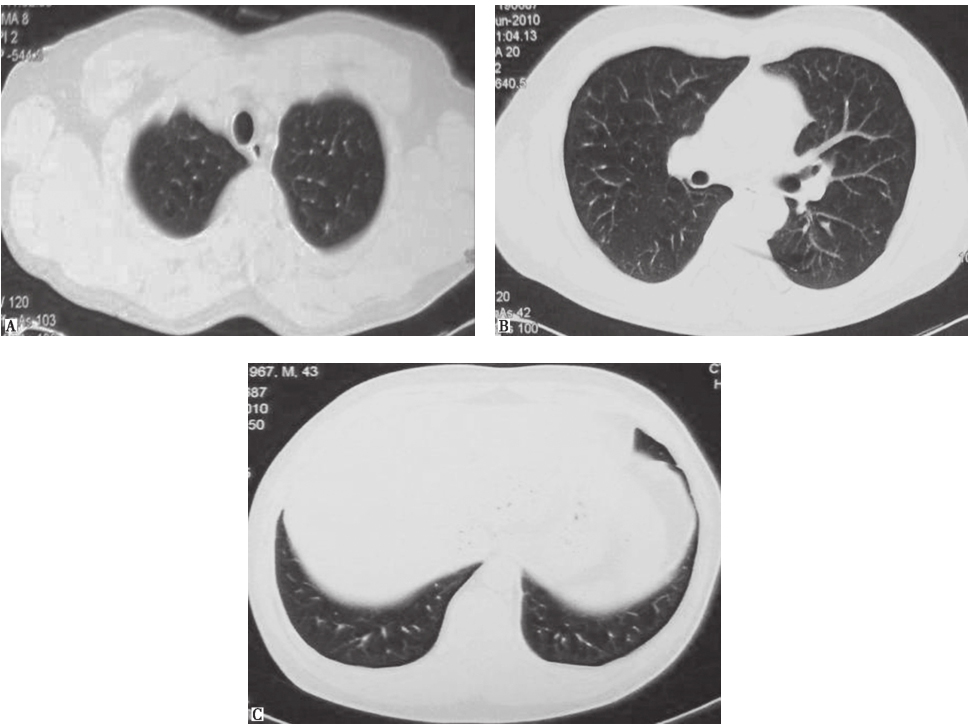

对于临床怀疑PLCH的患者,可以参考图5进行诊断和鉴别诊断。

图5PLCH诊断流程